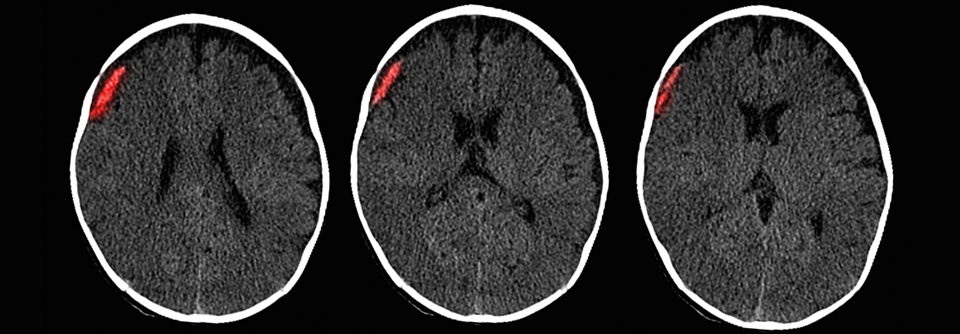

Subdurales Hämatom bei ein­em sechs Monate alten Säugling nach Kindesmisshandlung (vermutlich Schütteltrauma). Subdurales Hämatom bei ein­em sechs Monate alten Säugling nach Kindesmisshandlung (vermutlich Schütteltrauma). © Science Photo Library/Camazine, Scott